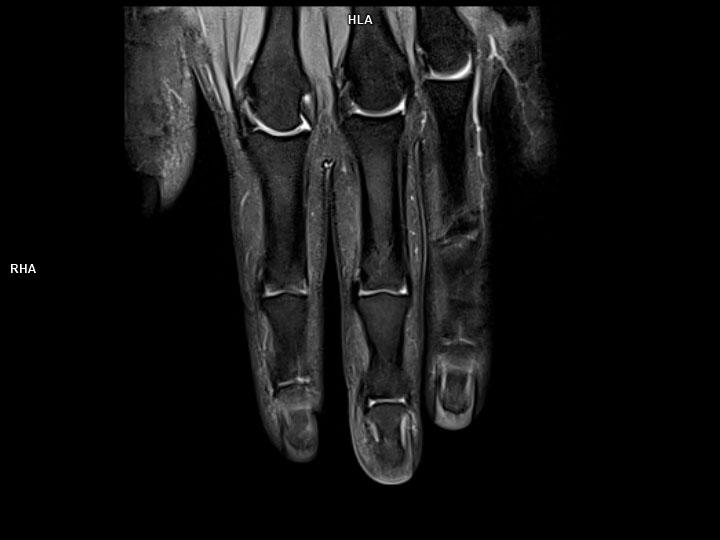

Coronal PD FS-MAGNETOM Lumina

Coronal PD FS-MAGNETOM Lumina/Coil-Hand Wrist 16/Resolution-384/Scan Time-1:54/Aceleration-p2